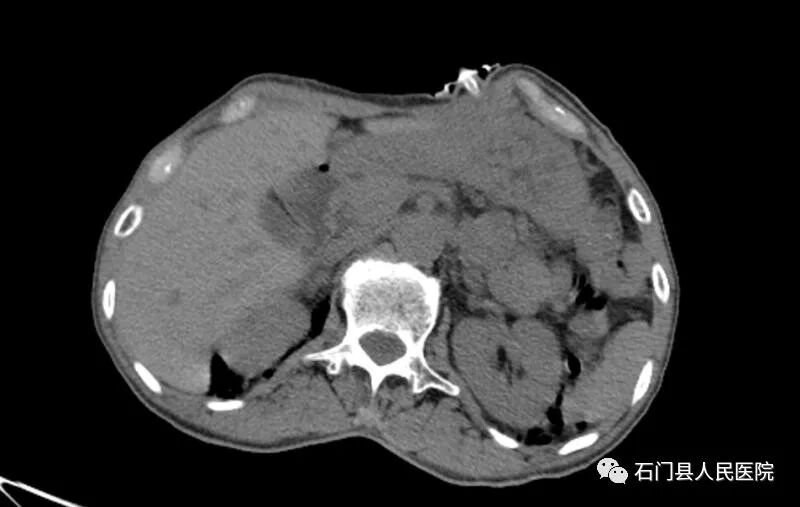

征得患者家属同意,刘斌主任在4月2日为患者完成X线引导下经皮胃造瘘术,手术顺利。目前患者通过造瘘管予以胃腔内注食改善营养状态后,转入肿瘤科继续接受放化疗治疗。

X线引导下经皮胃造瘘术最大的优点是具有操作简单、创伤小,手术时间短,患者耐受性好,留置的造瘘管较普通的鼻胃肠管耐用,留置时间长(可长达1—2年)、较鼻饲在一定程度上减少食物返流机会、降低肺部感染的发生、消除患者鼻咽部不适感、方便护理、美观等优点。

X线视引导下胃造瘘的优势是只需局部麻醉,即使在呼吸功能严重受损需呼吸机支持的患者,不受体位的影响,同样也可以顺利完成手术。